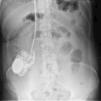

Se caracteriza por la manipulación, ya sea consciente, ya inconsciente, del generador de tales dispositivos, lo que origina el giro de este sobre sí mismo, lo que ocasiona el trenzado del cableado de estos sistemas, pudiendo provocar su rotura o bien el desplazamiento de los electrodos intracraneales.

Describimos un caso de síndrome de twiddler en un paciente tratado mediante estimulación cerebral profunda para el trastorno obsesivo compulsivo que, tras una buena respuesta inicial, presenta un deterioro clínico, apreciándose en las radiografías de control del sistema el giro del cableado y el desplazamiento de los electrodos intracraneales.

Characterised by manipulating either consciously or unconsciously the generator of such devices, which causes it to rotate on itself, the syndrome causes the coiling of the wiring of these systems and can lead to their rupture or the displacement of intracranial electrodes.

We describe a case of twiddler's syndrome in a patient treated with DBS for obsessive-compulsive disorder, in which clinical deterioration presented after a good initial response. Control radiographs revealed rotation of the wiring system and displacement of the intracranial electrodes.